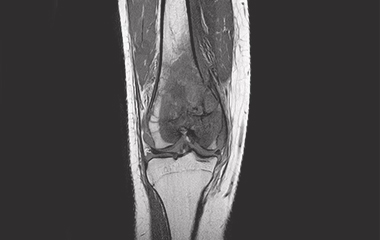

Conventional treatment of knee pain and resultant dysfunction currently does not adequately address the sources of pain due to difficulty visualizing, accessing and treating the intraosseous (bone marrow) lesion. Current clinical procedures and systems on the market only approximate the location of the lesion potentially providing a less precise clinical outcome as well as requiring fluoroscopy for localization and confirmation.

Management of early knee osteoarthritis presents a challenge for many orthopaedic surgeons and patients. Etiology from many of these patients originates from bone marrow lesions (subchondral edema) and if left untreated could lead to progressive pain, progression of arthritis, and subsequent need for knee arthroplasty(1).

The PanPlasty Instrument System is uniquely designed to precisely target and delivery biomaterials to ensure precise treatment of intraosseous lesions potentially lessening/alleviating patient pain and delaying the need for more complex and invasive arthroplasty surgical procedures.